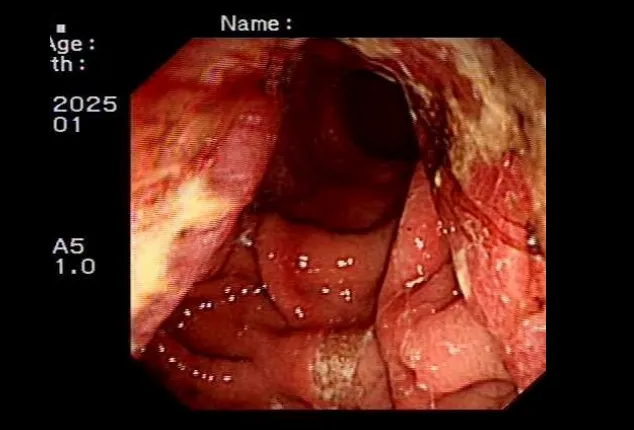

胃肠外科面对复杂、高风险的二次肿瘤手术展现出强大实力。一例66岁残胃癌复发患者,11年前曾行胃癌部分切除术,腹腔粘连严重,且合并肺气肿、营养不良等多重问题。胃肠外科牵头组织心内科、麻醉科、呼吸内科、影像科、临床营养科、中医科等进行多学科(MDT)会诊,制定了周详的个体化手术与围手术期管理方案。团队成功为患者实施了高难度的“残胃切除+食管空肠吻合+淋巴结清扫+粘连松解”手术。术后,针对患者出现的血压偏低等情况,心内科与中医科协同干预;临床营养科全程提供阶梯式营养支持。在多学科无缝协作下,患者平稳度过危险期,未发生严重并发症,顺利康复出院。该案例是我院利用多学科(MDT)综合诊疗模式优势处理复杂腹部肿瘤的成功典型案例。